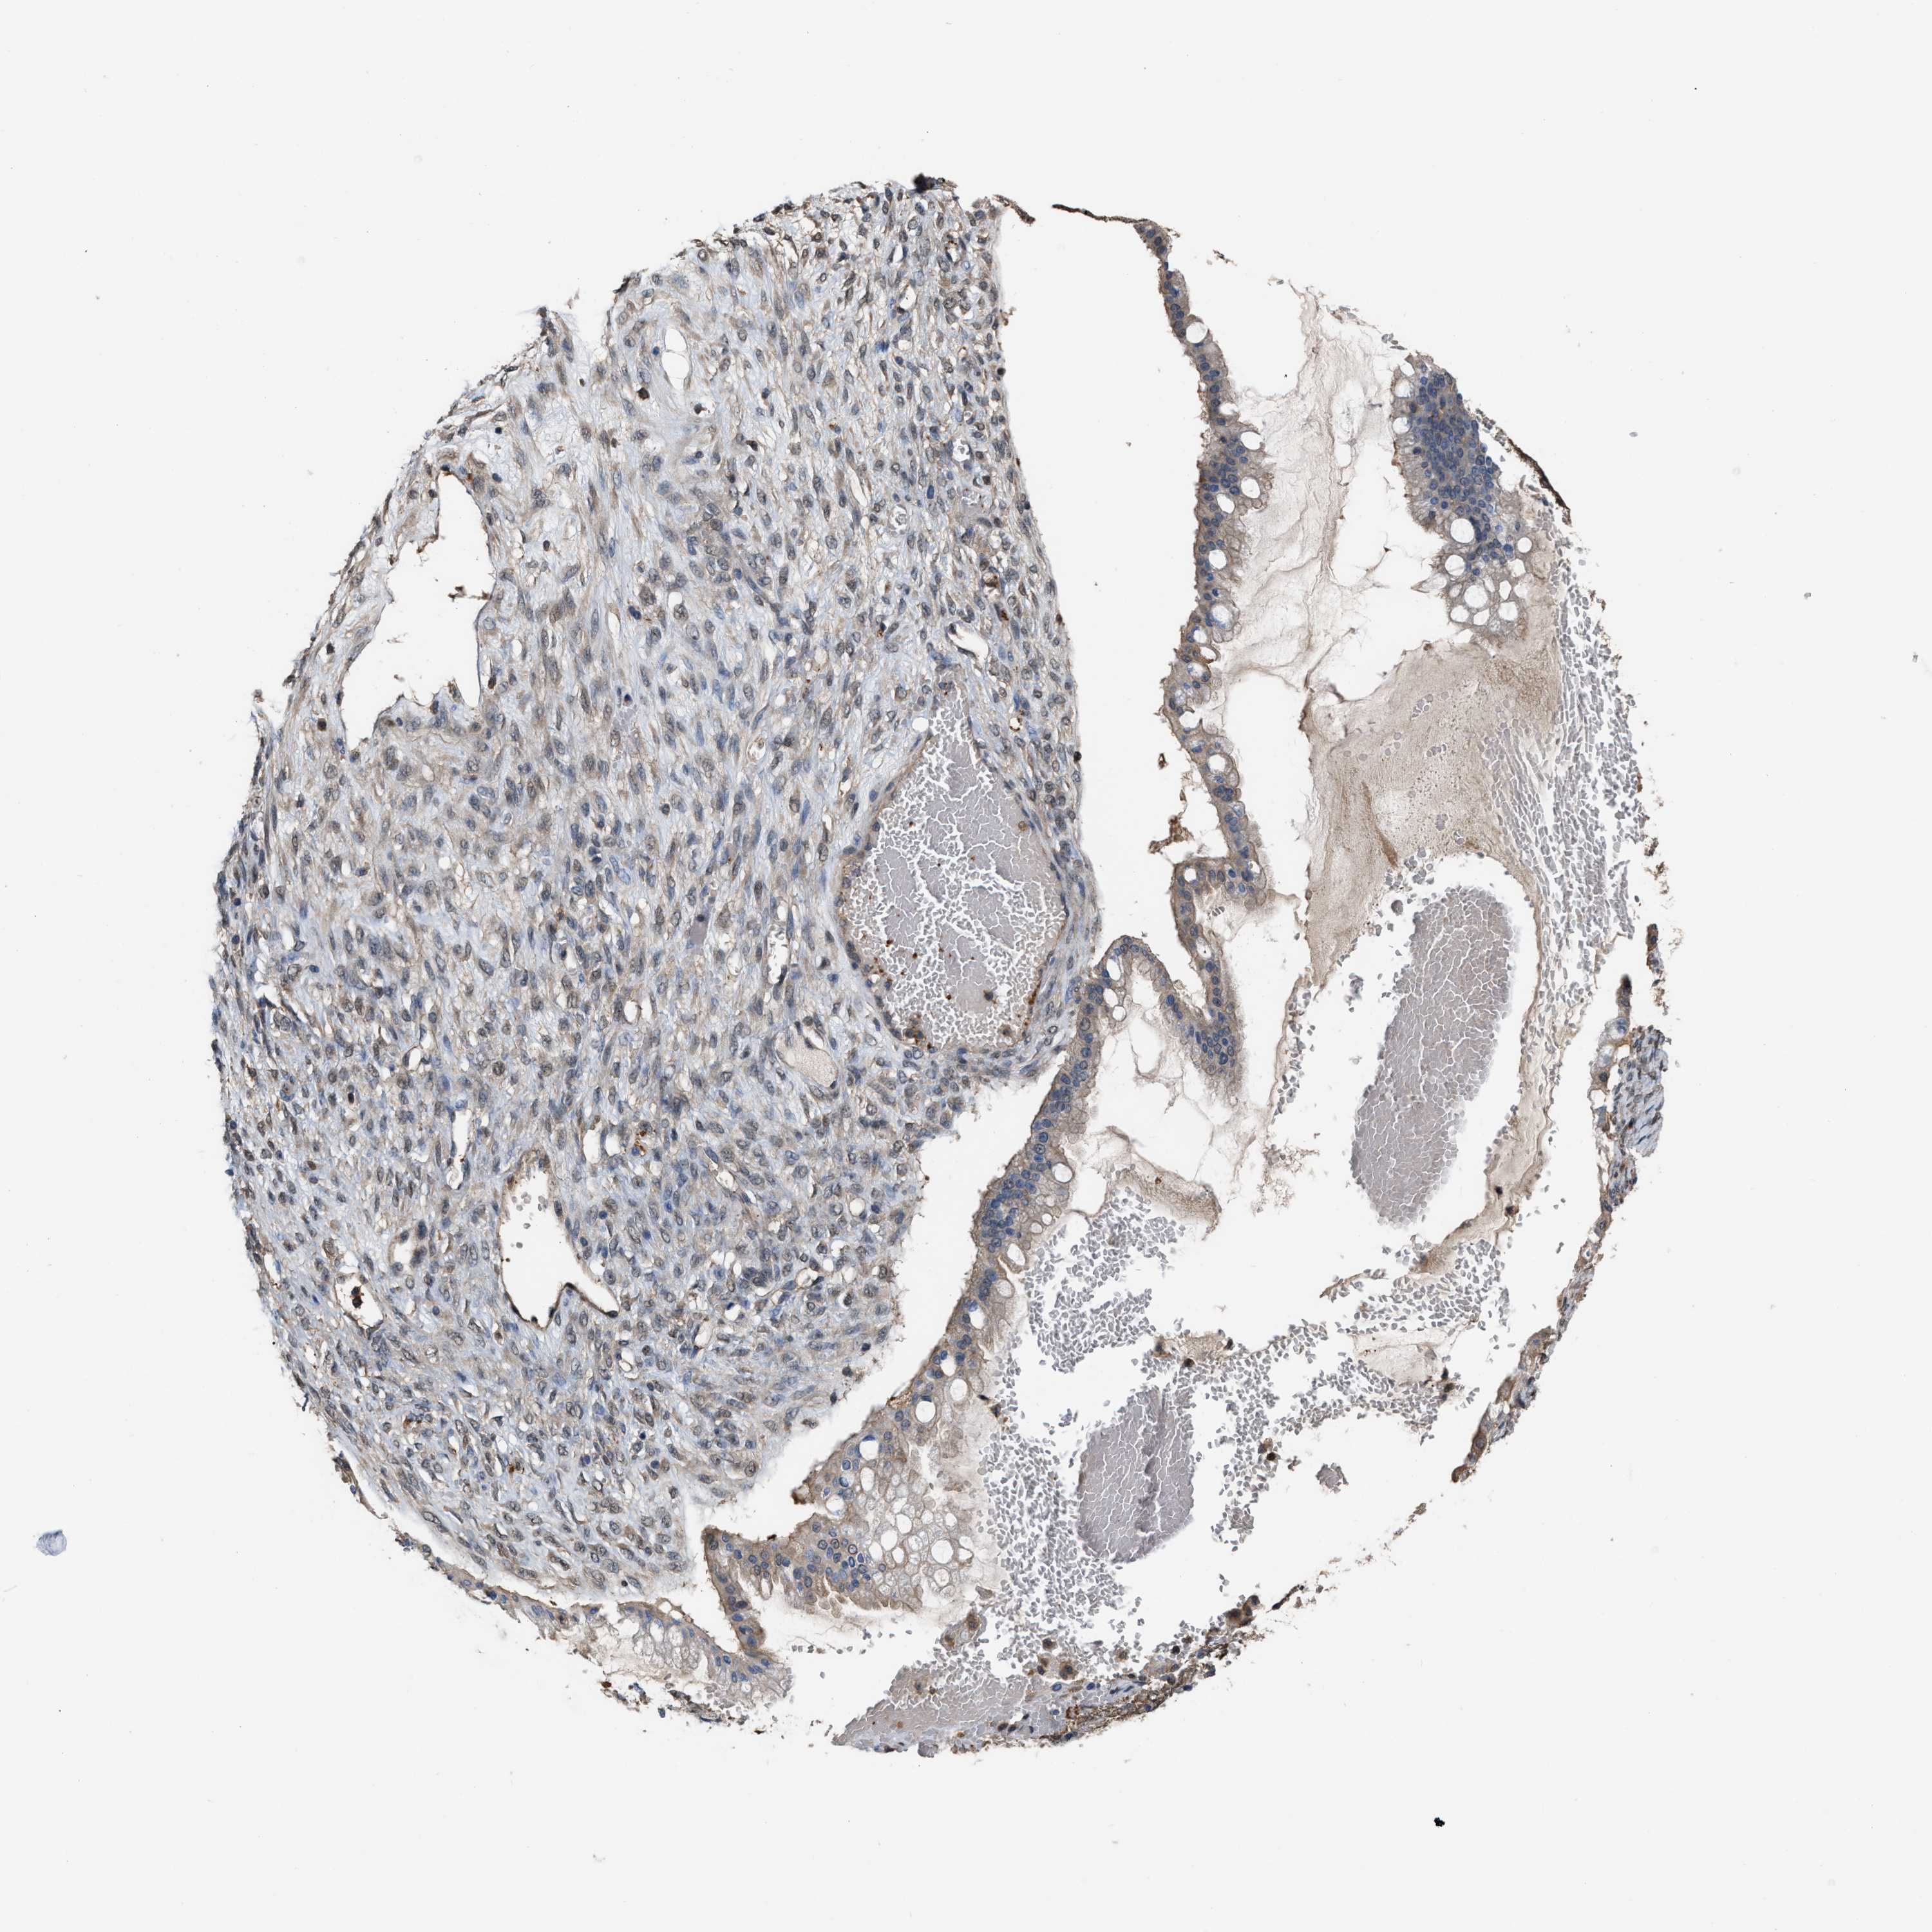

OVARIAN CANCER - Protein expressioni

A mouse-over function shows sample information and annotation data. Click on an image to view it in a full screen mode. Samples can be filtered based on level of antibody staining by selecting one or several of the following categories: high, medium, low and not detected. The assay and annotation is described here.

Note that samples used for immunohistochemistry by the Human Protein Atlas do not correspond to samples in the TCGA dataset.

Antibody stainingi

Antibody staining in the annotated cell types in the current human tissue is reported as not detected, low, medium, or high, based on conventional immunohistochemistry profiling in selected tissues. This score is based on the combination of the staining intensity and fraction of stained cells.

Each image is clickable and will lead to virtual microscopy that enables deeper exploration of all samples and also displays staining intensity scores, fraction scores and subcellular localization as well as patient and tissue information for each sample.

Antibody HPA019735

Staining

High

Medium

Low

Not detected

Intensity

Strong

Moderate

Weak

Negative

Quantity

>75%

75%-25%

<25%

None

Location

Nuclear

Cytoplasmic/membranous

Cytoplasmic/membranous,nuclear

Cystadenocarcinoma, serous, NOS

Carcinoma, endometroid

Cystadenocarcinoma, mucinous, NOS

Carcinoma, NOS